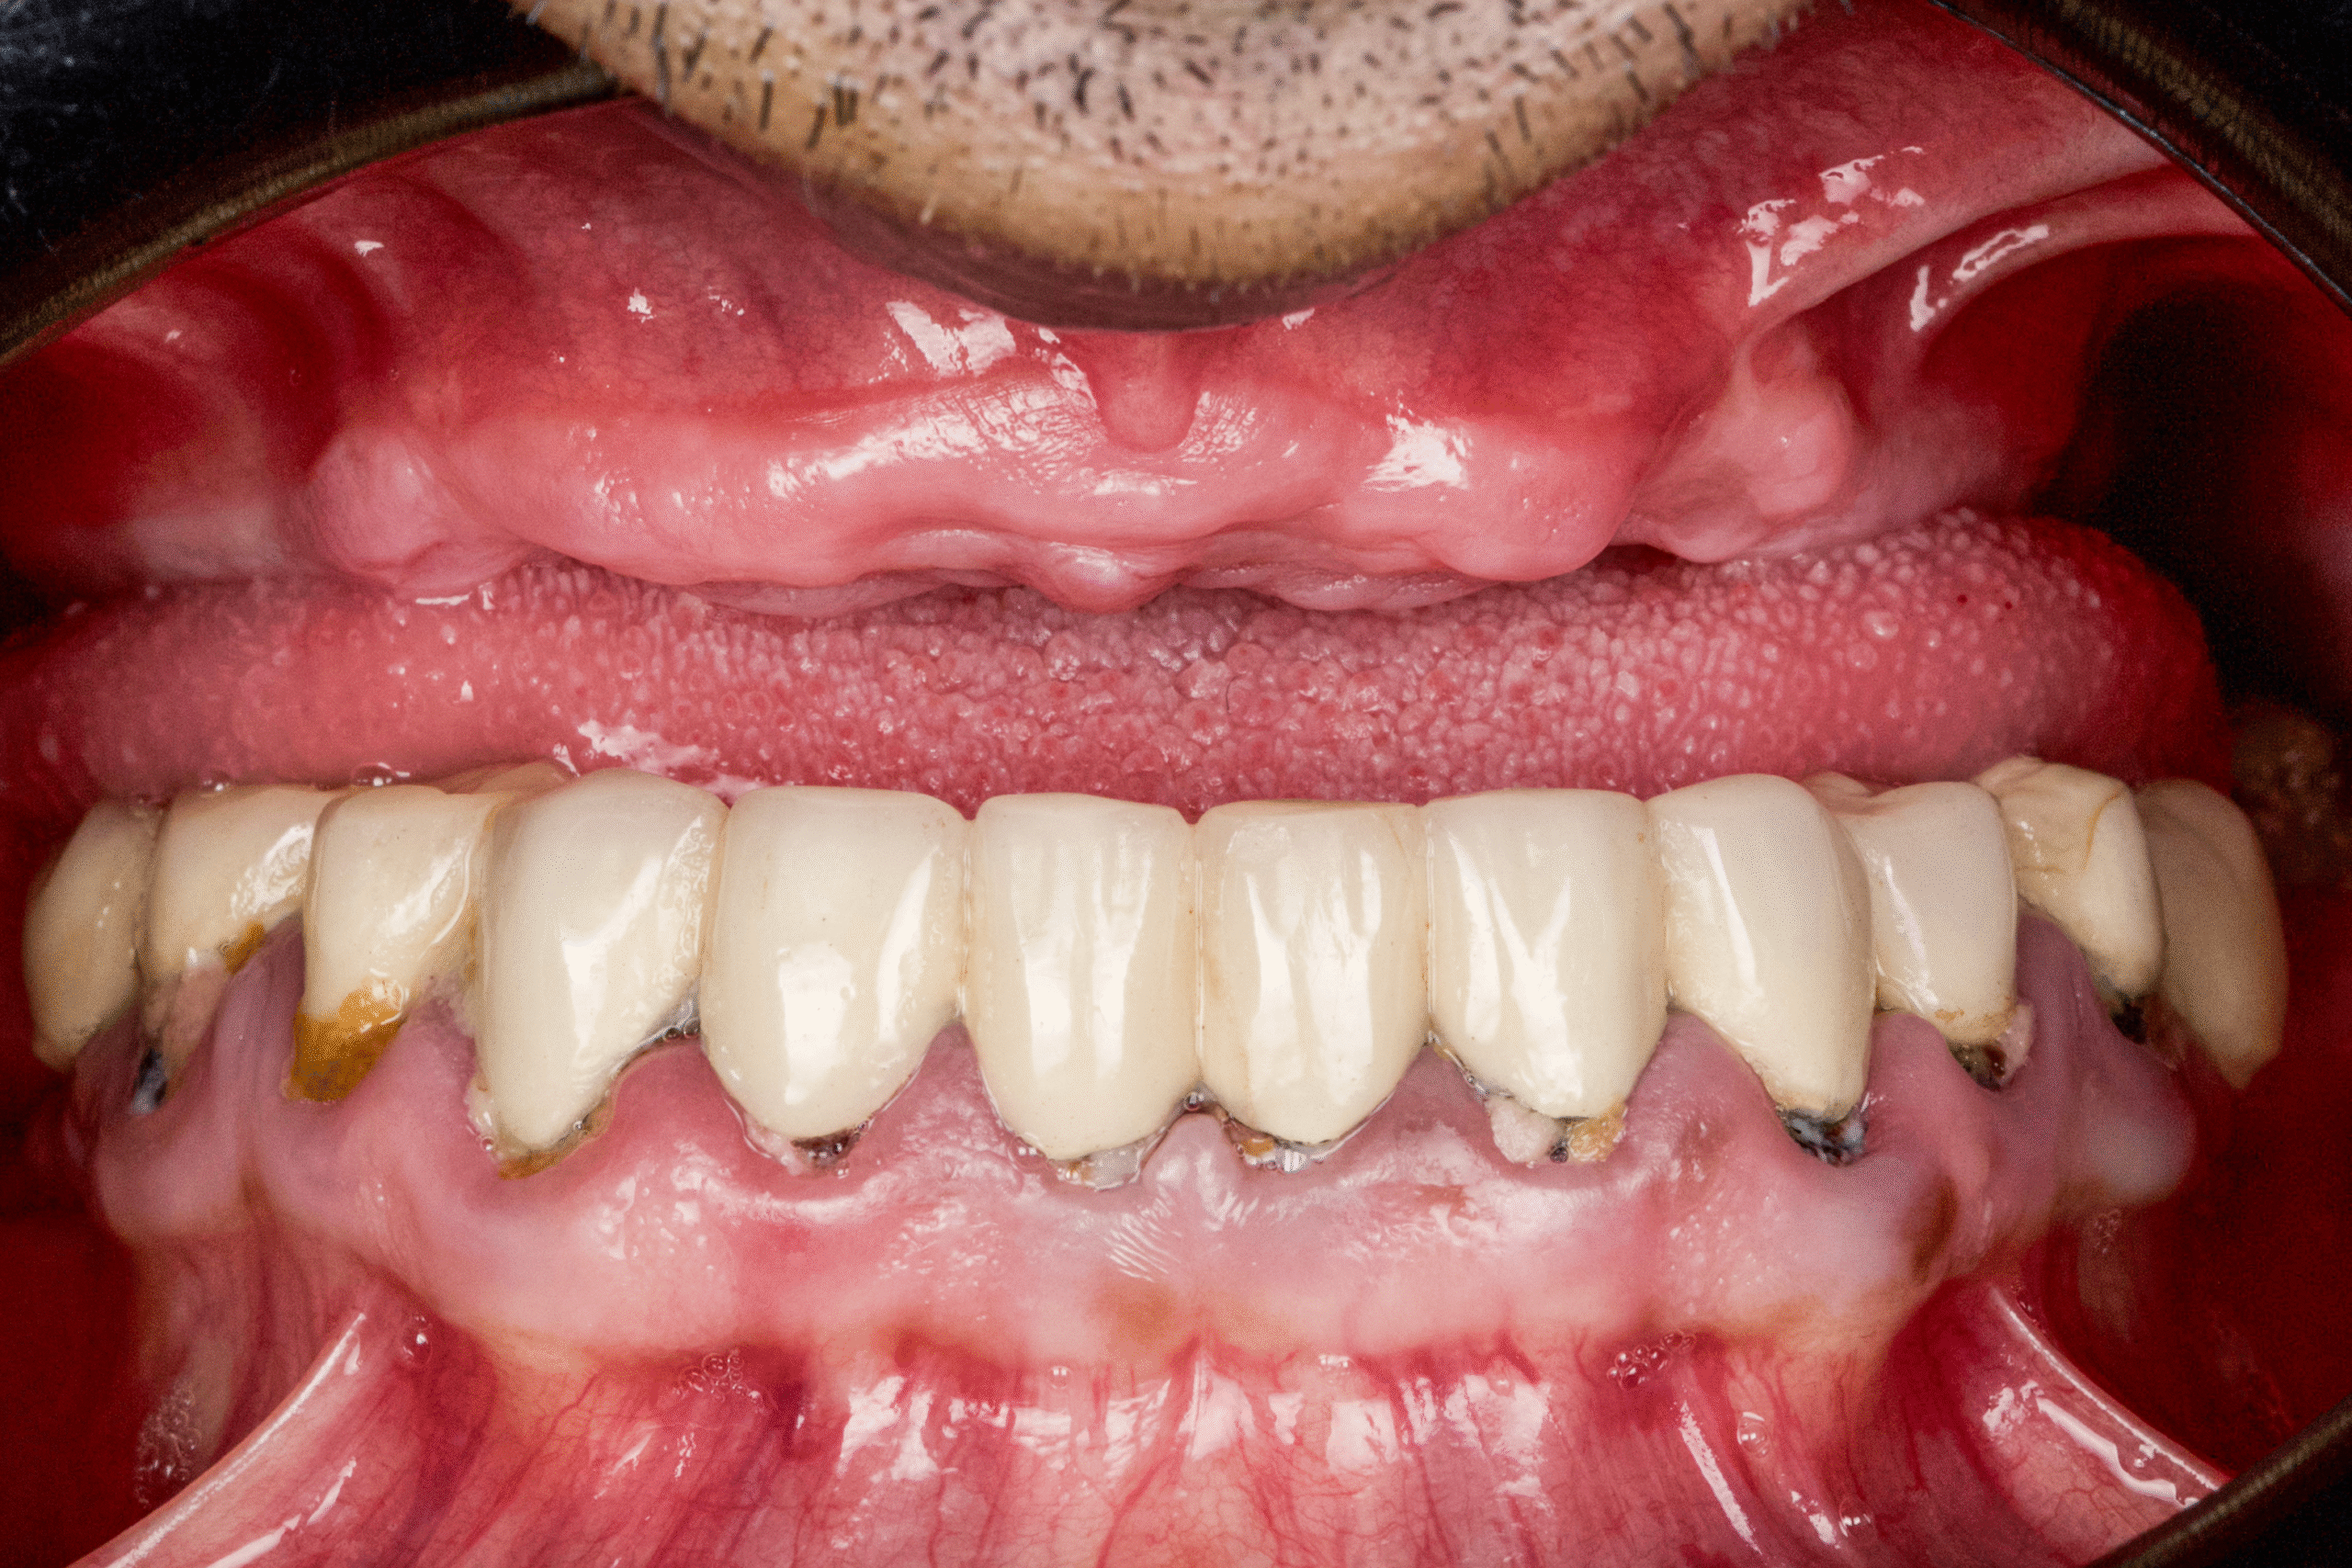

In only 3 hours, James received a complete upper-jaw reconstruction and a corrected lower-arch restoration using a fully flapless implant technique.

He left the clinic the same day with:

- A functional temporary smile

- A dramatically improved ability to speak and chew